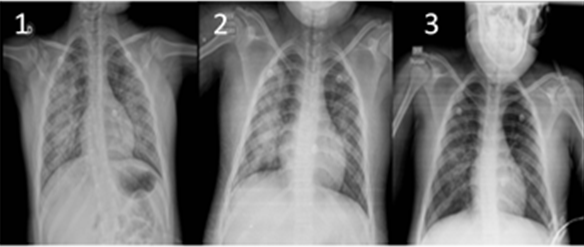

Imagen 1. Imágenes radiológicas del paciente. 1 se observan infiltrados alveolares perihiliares bilaterales. 2 se observan infiltrado intersticio alveolares perihiliares bilaterales, senos costodiafragmáticos libres. 3 infiltrado intersticial a predominio de hemitórax derecho, reforzamiento hiliar bilateral, ángulos costofrénicos libres.

A su admisión, se presenta febril (38°C), con piel pálida y mucosas secas, taquicárdica (130 latidos por minuto), con llenado capilar de 3 segundos; al examen físico resalta polipnea (FR 35 por minuto, percentil 90 para su edad) a pesar de no evidenciar esfuerzo respiratorio, se constató desaturación en rango 81 a 90 %, acompañado a la percusión en ambos tercios inferiores del tórax con vibraciones vocales y murmullo vesicular disminuido, a la auscultación estertores crepitantes bilaterales, sin datos de obstrucción bronquial. Los estudios complementarios a su ingreso destacan: hemograma con 8077 glóbulos blancos, 77 % de neutrófilos y PCR elevada. Radiografía de tórax con imágenes de infiltrado alveolar en ambas bases pulmonares (imagen 1, 1).

Se inició tratamiento antibiótico para gérmenes más frecuentes por grupo etario con amoxicilina más ácido clavulánico, previa toma de hemocultivos por dos. Sin embargo, ante clínica desfavorable durante las primeras horas de hospitalización, además de su grupo etario, patrón radiológico y antecedentes epidemiológicos (familiares con cuadros respiratorios de evolución subaguda) se sospecha de neumonía por gérmenes atípicos y solicita serología de Mycoplasma pneumoniae y además se decide ampliar cobertura antibiótica a cefalosporina de 3ª generación más claritromicina para cubrir gérmenes atípicos. En su cuarto día de hospitalización la serología de Mycoplasma se reportó positiva, confirmando el diagnóstico. Sin embargo, debido a controles de radiográficos de tórax seriados (figura 1, 2 y 3) en iguales condiciones se consideró realizar estudios de BDK en aspirado gástrico como parte de su abordaje, los cuales resultaron negativos. Los hemocultivos resultaron negativos por dos.